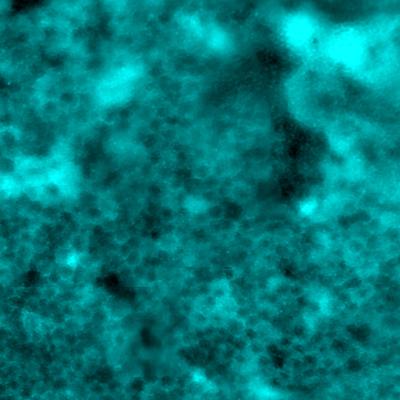

retinal pigment epithelial cells as seen by adaptive optics fluorescence microscopy

Mosaicism in the retinal pigment epithelial cells as seen by adaptive optics fluorescence microscopy. A stable fluorescence pattern is observed in human eyes following labeling by indocyanine green dye.

Read the associated publication.

View the video: Imaging method reveals long-lived patterns in cells of the eye